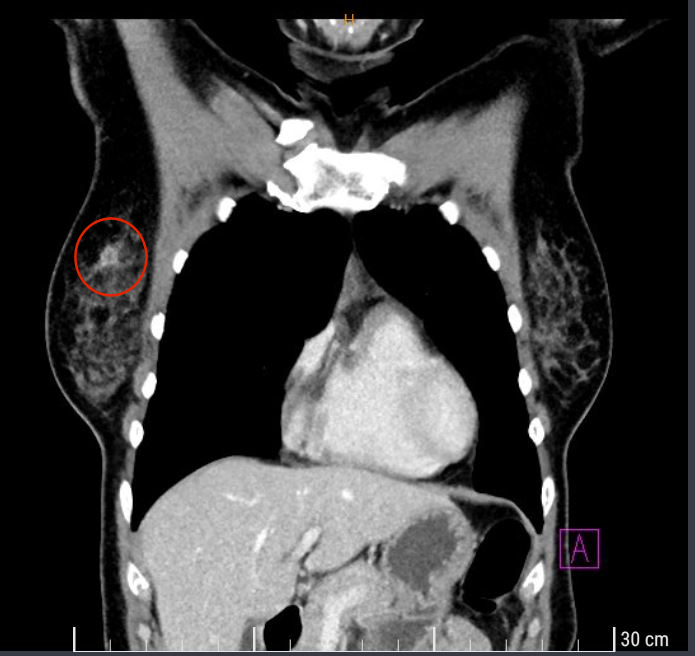

Dann ruft mich der Arzt zu sich ins Büro. Wie ich wahrscheinlich schon weiss, befindet sich in meiner rechten Brust ein 13 mm im Durchmesser messender annormaler Bereich, ein Tumor. Daneben sieht meine Lunge top aus. Galle, Bauchspeicheldrüse, Milz und Nieren seinen unauffällig und metastasenfrei. Ich habe zwar eine Fettleber (!?), aber ohne Metastasen. Auch gynäkologisch keine Auffälligkeiten.

Er hätte vergessen: In der rechten Achsel zeigten sich mehrere bis zu 20 mm im Durchmesser

messende Lymphknoten, hier muss sicher primär von einer Metastasierung ausgegangen werden.

Er zeigt auf den Bildschirm. Ja, das hatte ich ja bereits befürchtet. Auf den Aufnahmen des CTs kann man ziemlich deutlich Brustkrebs und die betreffenden Lymphknoten erkennen, die dagegen auf der linken Seite unsichtbar sind.